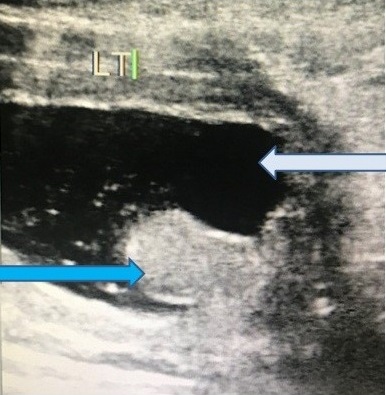

Fibroepithelial Polyp of Urethra Presenting with Acute Urinary Retention